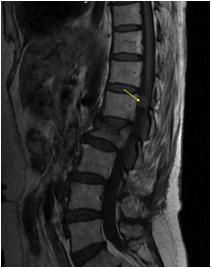

We found a strong positive correlation between abnormal EEG and abnormal Neuroimaging with Correlation coefficient of 0.902, (P- Value 0.0138) but almost no correlation found between normal EEG with normal Neuroimaging (Figs 1-4).

About 23% of patients with adult onset first seizure has metabolic derangement and the most common etiology was Dyselectrolytemia. The most common Central Nervous System (CNS) Infection as detected by CSF study was viral meningoencephalitis followed by Tuberculous Meningitis. The most common CNS lesion detected by CT studies as well as by MRI Brain was infarction and ring lesion, the two Neuroimaging studies corroborated in 75.38% of Seizure patients. Abnormal discharge in EEG found in34% cases. In majority patients EEG report was normal. EEG abnormality was more common in patients with Focal Seizure rather than GTCS patients. Thus, the most common etiology of first Seizure onset at adult age over 18 years were metabolic derangements (16.92%), CNS Infection or Inflammation (15.38%) and intracerebral Space occupying lesion (15.38%), usually ring lesion, tumors and Metastasis. Idiopathic Seizure found in 7.69% patients. The Correlation between abnormal Neuroimaging and abnormal EEG is strongly positive and statistically significant (P -Value = 0.013) but the same is not true in cases of normal Neuroimaging and normal EEG findings.